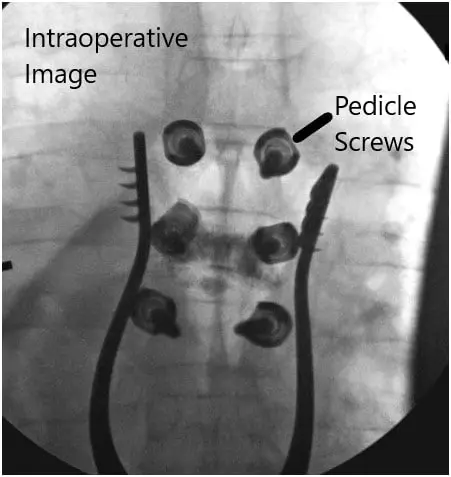

Intraoperative fluoroscopic images.

Using anatomic trajectories, we then tapped these pedicles to start and inserted 4.5 x 30 mm pedicle screws on both sides. We confirmed our trajectories using fluoroscopy and triggered EMG. We did the same thing for both the T5 and T7 pedicles probing them using Lenke gearshifts and under fluoroscopy after creating our pilot hole with normal anatomical starting points with the high-speed drill. We inserted 5.5 x 40 mm screws under direct fluoroscopy at the T5 and T7 levels and then applied 5.5 x 65 mm rods, which were secured with caps screws and locked into position.

All six screws were stimulated using trigger EMGs and found to be in a safe position. We then obtained both the final AP and lateral x-rays to ensure the proper positioning of the screws. The wound was washed out copiously with bacitracin irrigation and then the high-speed drill was used to decorticate the bone and the bone chips obtained were then gathered, morselized, and used for autograft.